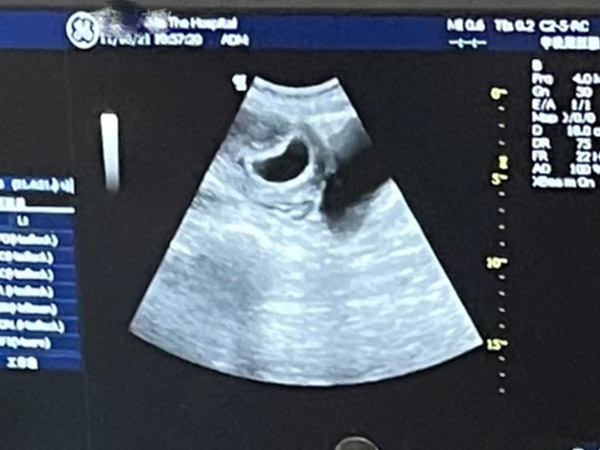

孕8周有胎心胎芽後HCG和孕酮漲不漲還是比較重要的,這時千萬不要大意,因為對於胎兒來說,懷孕前三個月的干擾因素較多,寶寶發育還不夠穩定,如果沒有HCG和孕酮的支援,可能會出現發育遲緩或胎停的情況,所以孕媽要按時去醫院產檢檢視hcg和孕酮,如果hcg和孕酮沒有上漲且有下降的趨勢,要及時採取相應措施。不過懷孕是個優勝劣汰的過程,如果醫生認為胎兒發育潛力較小,沒有必要保胎的話就不要勉強,以免生下有先天缺陷的孩子。

其實,除了hcg和孕酮外,大多數醫院還會讓孕媽在懷孕初期監測雌二醇水平,就算有了胎心胎芽這幾項激素的數值仍然具有參考價值,因為它們在維持妊娠方面發揮著非常關鍵的作用,具體如下: